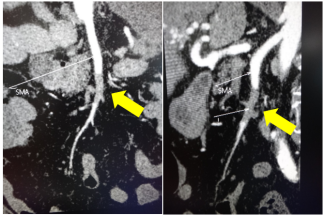

★ 案例四

67岁患者,突发下腹痛2天,既往房颤未系统治疗,全腹增强CT提示肠系膜上动脉血栓、肠梗阻。

切除后仅剩80cm小肠,通过精心的围手术期管理和长期的家庭肠外营养支持,成功存活。这不仅考验外科技术,更考验整个团队的综合管理能力。

★ 案例五

全腹持续性腹痛2天;诊断:肠系膜上动脉(分支)闭塞、脾梗死、房颤和弥漫性腹膜炎;查体:全腹压痛、反跳痛伴肌紧张,右侧下腹部腹痛较重;行右半结肠切除术、肠系膜上动脉取栓术,术后经历感染休克关,现患者恢复良好,于血管外科病房治疗中。